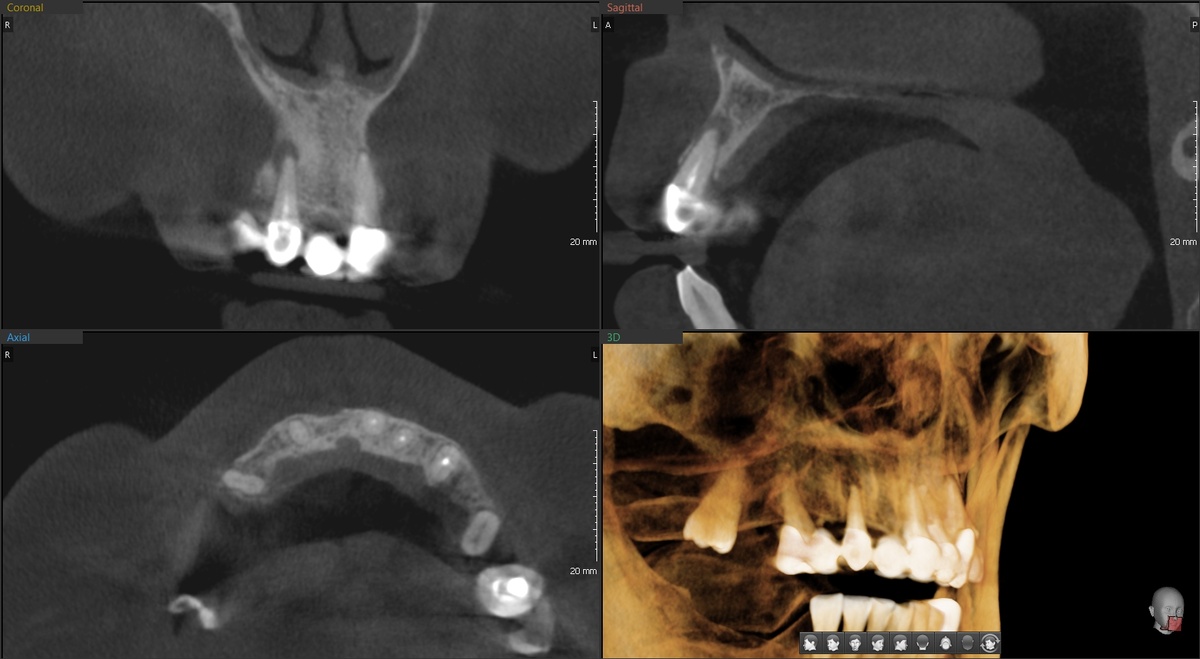

Важный нюанс - птеригоидные имплантаты не нагружаем сразу после операции. Они длинные (20-25 мм), стоят в относительно мягкой кости. Да, за счёт длины они устойчивы к смещению - их безопасно оставлять без нагрузки на длительный срок.

Поэтому протез опирается в только на 4 передних имплантата:

В основании протеза (то, что прилегает к десне) - индивидуальная титановая балка. Гладкая, полированная. К ней не липнет налёт, она держит все имплантаты в жёсткой связке.

Десна сохранила природоподобные контуры:

Никакой "сосиски" вместо естественных сосочков.